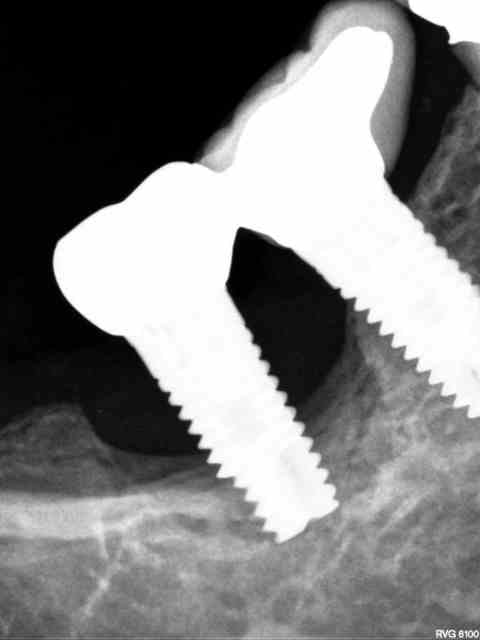

à mon humble avis, après séparation des couronnes, les quelques spires restantes semblent être dans un os D4 voir même fibrose au pourtour, devrais pas résister beaucoup

flic flac, il ne suffit pas de dire à mon humble avis ( ne le prends pas mal c'est pas mon intention) car deux ou trois spires peuvent avoir une résistance incroyable. Il y a un mois j'ai dû déposer un WP posé par un confrère il a 4 ans avec 3 spires qui restaient intégrées, le tourne à gauche s'est cassé, le davier restait inefficace, et j'ai dû carotter autour pour le déposer car comme toi, en voyant la radio, je pensais que c'était facile.

Le cas que tu présente, les spires sont dans de l'os D1

(corticale) tandis que l'autre cas l'os est vraiment de faible densité.